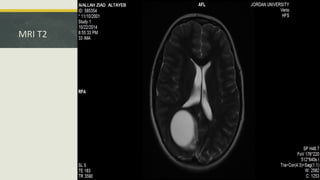

MRI T2

• #18 Emphasizes the vasogenic edema in these images.

• #19 There is a linear, mural enhancement on the medial aspect of its parasagittal border. no other areas of abnormal enhancement in other parts of the brain parenchyma, either in the ventricular system or the subarachnoid space